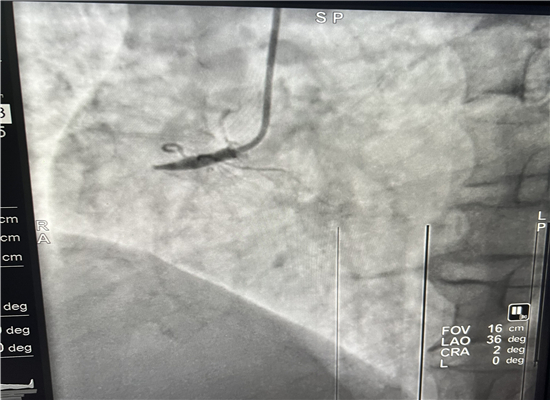

19时13分左右,一名患者因晚饭后行走不稳而请求出诊,急诊医学科医护人员火速赶往现场,到诊时测生命体征,输液后接回急诊医学科,回科后做心电图检查,诊断为急性心肌梗塞,随即通知心血管内科会诊,确定做急诊介入治疗,20时30分进入导管室,杨勇主任、张轩副主任共用21分钟就实现了心肌再灌注,挽救了患者生命。

介入手术后